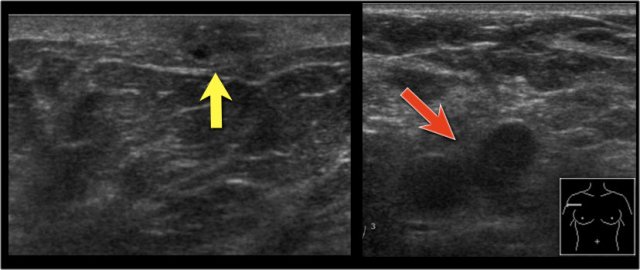

On this ultrasound image, there is another satellite nodule within the skin (yellow arrow).

Multiple enlarged axillary nodes are seen (red arrow).

Fine needle aspiration demonstrated metastases within these nodes.

This tumor was staged as T4bN+. This means that we are dealing with locoregionally advanced disease.

These patients are at risk for systemic disease and additional imaging was performed.